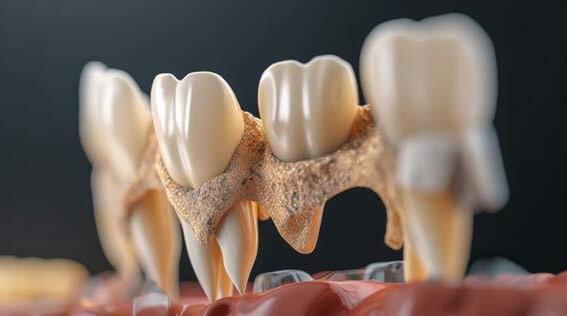

Por qué la Generación Z debe abrazar la salud de las encías

Bruselas, 22 de abril de 2024. A medida que la Generación Z comienza su viaje hacia la adultez, hay un aspecto crucial de la salud que a veces pueden pasarse por alto: sus encías. Con el aumento de las dietas azucaradas y los niveles crecientes de estrés y ansiedad, los adolescentes y adultos jóvenes son cada vez más susceptibles a enfermedades de las encías y otros problemas bucales. Este es el tema del Día de la Salud de las Encías 2024, una campaña anual de salud pública global liderada por la EFP (Federación Europea de Periodoncia).

Lanzado hace 10 años, el Día de la Salud de las Encías tiene como objetivo informar al público en general sobre los efectos perjudiciales de las enfermedades de las encías (gingivitis, periodontitis, mucositis periimplantaria y periimplantitis) tanto en la salud bucal como en la salud en general; así como las ventajas de mantener sus encías saludables desde una edad temprana.

Las enfermedades de las encías están asociadas con importantes problemas de salud sistémica, incluyendo diabetes, infarto de miocardio, insuficiencia cardíaca, accidente cerebrovascular, enfermedad renal crónica, resultados adversos en el embarazo, artritis reumatoide, enfermedad de Alzheimer, disfunción eréctil, ciertas formas de cáncer y otras enfermedades sistémicas. Al cuidar nuestras encías, todos podemos empezar a prevenir esos problemas de inmediato, ya que una sonrisa sana puede allanar el camino hacia un estilo de vida más saludable, e incluso ahorrar dinero en el futuro.